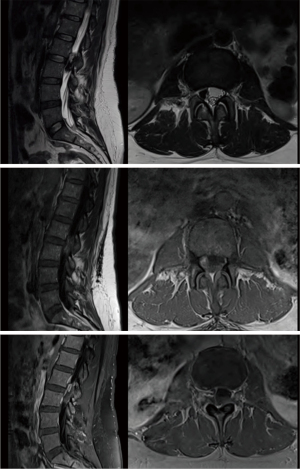

The patient had continued subjective improvement of symptoms over the following two days and was subsequently discharged on hospital day 8 with plans to follow up with her primary hematologist and radiation oncologist. She completed her scheduled course of radiation treatment over an elapsed time of 15 days. At final follow up visit 3 months after initial ER presentation, she had complete resolution of her symptoms with normal sensation and full strength throughout. A post-treatment MRI revealed full radiographic eradication of the compressive hematopoietic lesion (Figure 3).

In our case, a 52-year-old female with sickle cell anemia presented with acute lumbar stenosis from extramedullary hematopoiesis, and conservative management via low-dose radiation therapy was initiated. Given her moderate neurological symptoms, radiotherapy offered a non-invasive treatment option while minimizing the risks associated with surgery, such as complications from anesthesia and hematological stress. Radiotherapy at a total dose of 2,400 cGy administered in 200 cGy increments over a period of 15 days proved highly effective for our patient, with complete resolution of symptoms at the final follow-up 3 months later. An MRI conducted 17 days after the final radiation session revealed complete resolution of the soft tissue signal in the right lateral epidural space at the L2–L3 level, confirming successful eradication of the EMH mass.